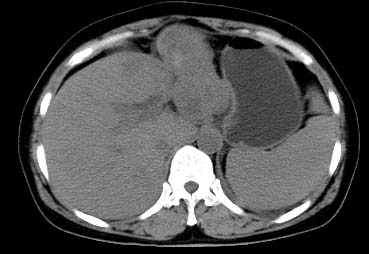

以下是引用西北一只狼在2008-6-30 20:58:00的发言:[br]肝左叶胆管细胞ca并肝门淋巴结转移、胰腺、胃小弯浸润

以下是引用ydx_74在2008-6-30 21:54:00的发言:[br]左叶胆管细胞ca并肝门淋巴结转移、胰腺、胃小弯浸润